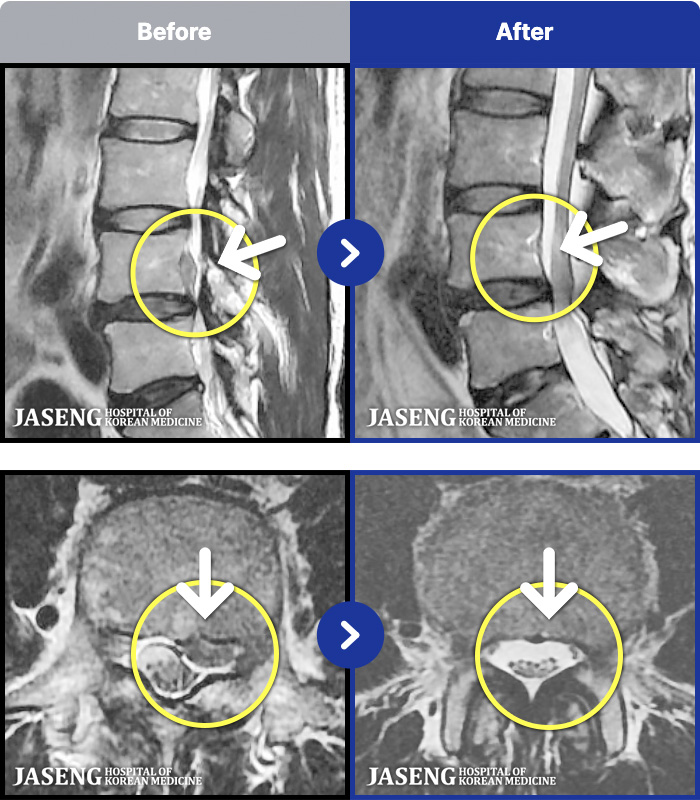

MRI ġ

MRI ũ ʸ Ȯϼ.